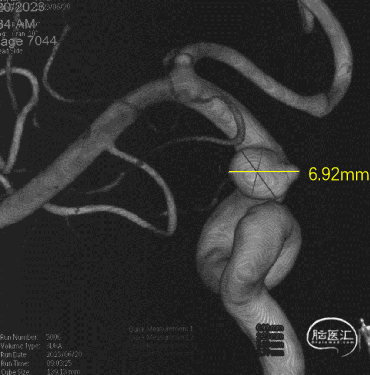

可见一小泡自动脉瘤瘤体上发出

瘤体最大径6.92mm

远端血管直径:3.28mm

近端血管直径:3.98mm

同侧A1可见一小瘤突起